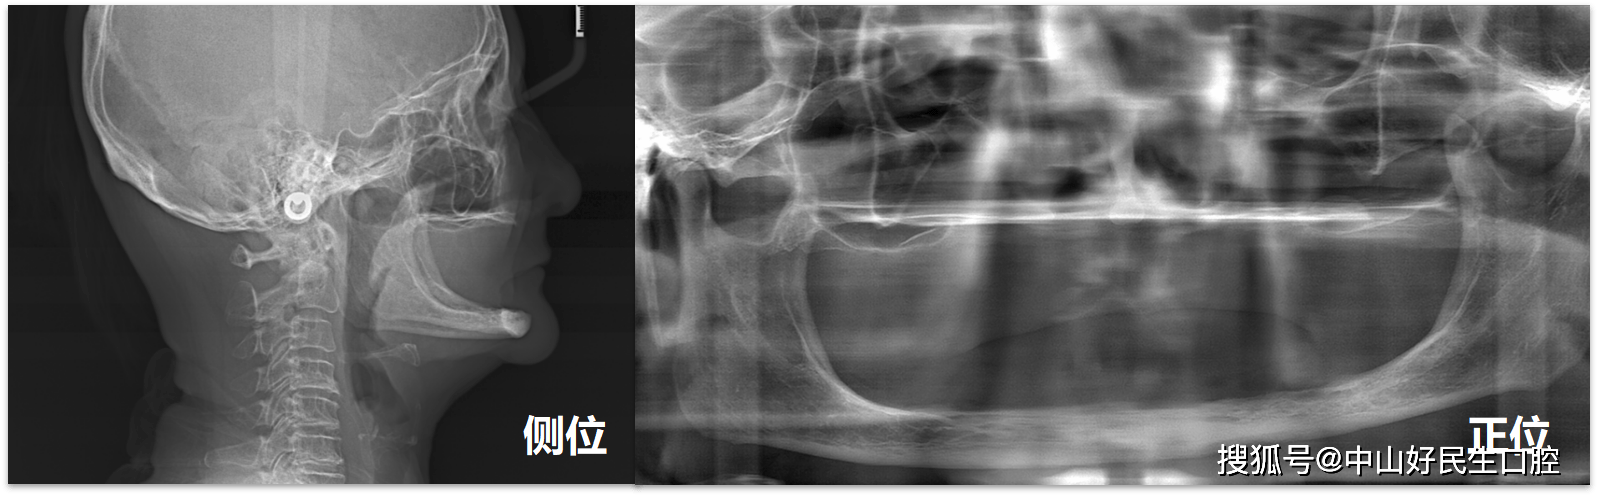

患者全口牙缺失 , 是真正的一望无牙 , 多年来都是依靠活动假牙生活 。 因旧的假牙折断 , 到本院就诊 。 因为缺牙多年 , 上下牙槽骨已极重度萎缩吸收 , 从X光片上可以看到 , 牙槽骨已从正常的“一块”缩减至“一条” 。 若考虑做种植牙 , 常规的种植方式和种植体已经无法实现 。 需要用较长的种植体 , 深入种植到面颊部颧骨 , 以增强稳固性 。 (穿颧种植术)